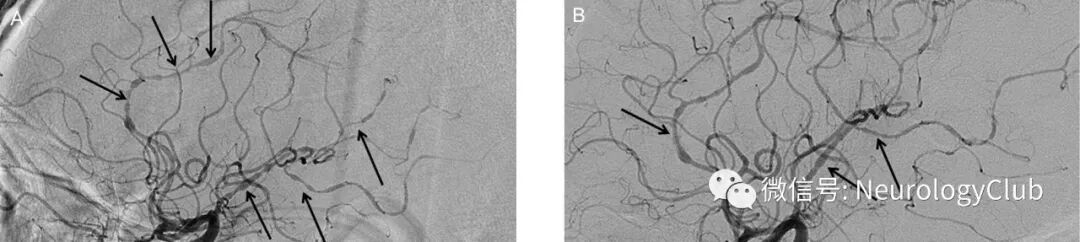

52岁男性,因扩张型心肌病所致终末期心功能衰竭行心脏移植。术后第8天,患者出现全面强直-阵挛发作。发作间期脑电图未见明显异常,实验室检查无殊。行头颅MRI和MRA检查。可见大脑半球后部多发T2高信号病灶。未见急性脑梗死或颅内血管异常(图1)。考虑为他克莫司治疗所致的PRES。为避免病情恶化,将他克莫司减量维持在正常血药浓度下限。此外,严格控制血压防止脑水肿加重。数小时后患者完全恢复。术后第18天,患者出现意识状态改变伴双侧肌力下降(2级)。影像学提示双侧额顶枕叶新发急性梗死以及多处脑血管弥漫狭窄(图2)。行DSA检查提示经典的脑动脉腊肠样外观,是RCVS的特征性改变(图3A)。实验室检查无血管炎相关证据。停用他克莫司,并给予尼莫地平治疗。患者血管痉挛较前改善(图3B)。左上肢肌力恢复至3级。随访3月,影像学未见新发梗死和血管收缩改变,但肢体肌力尚未完全恢复伴视敏度下降。

(图1:A:T2WI可见多发皮质-皮质下高信号病灶;B:ADC上病灶亦呈高信号;C:对应的DWI正常;D:MRA无殊)